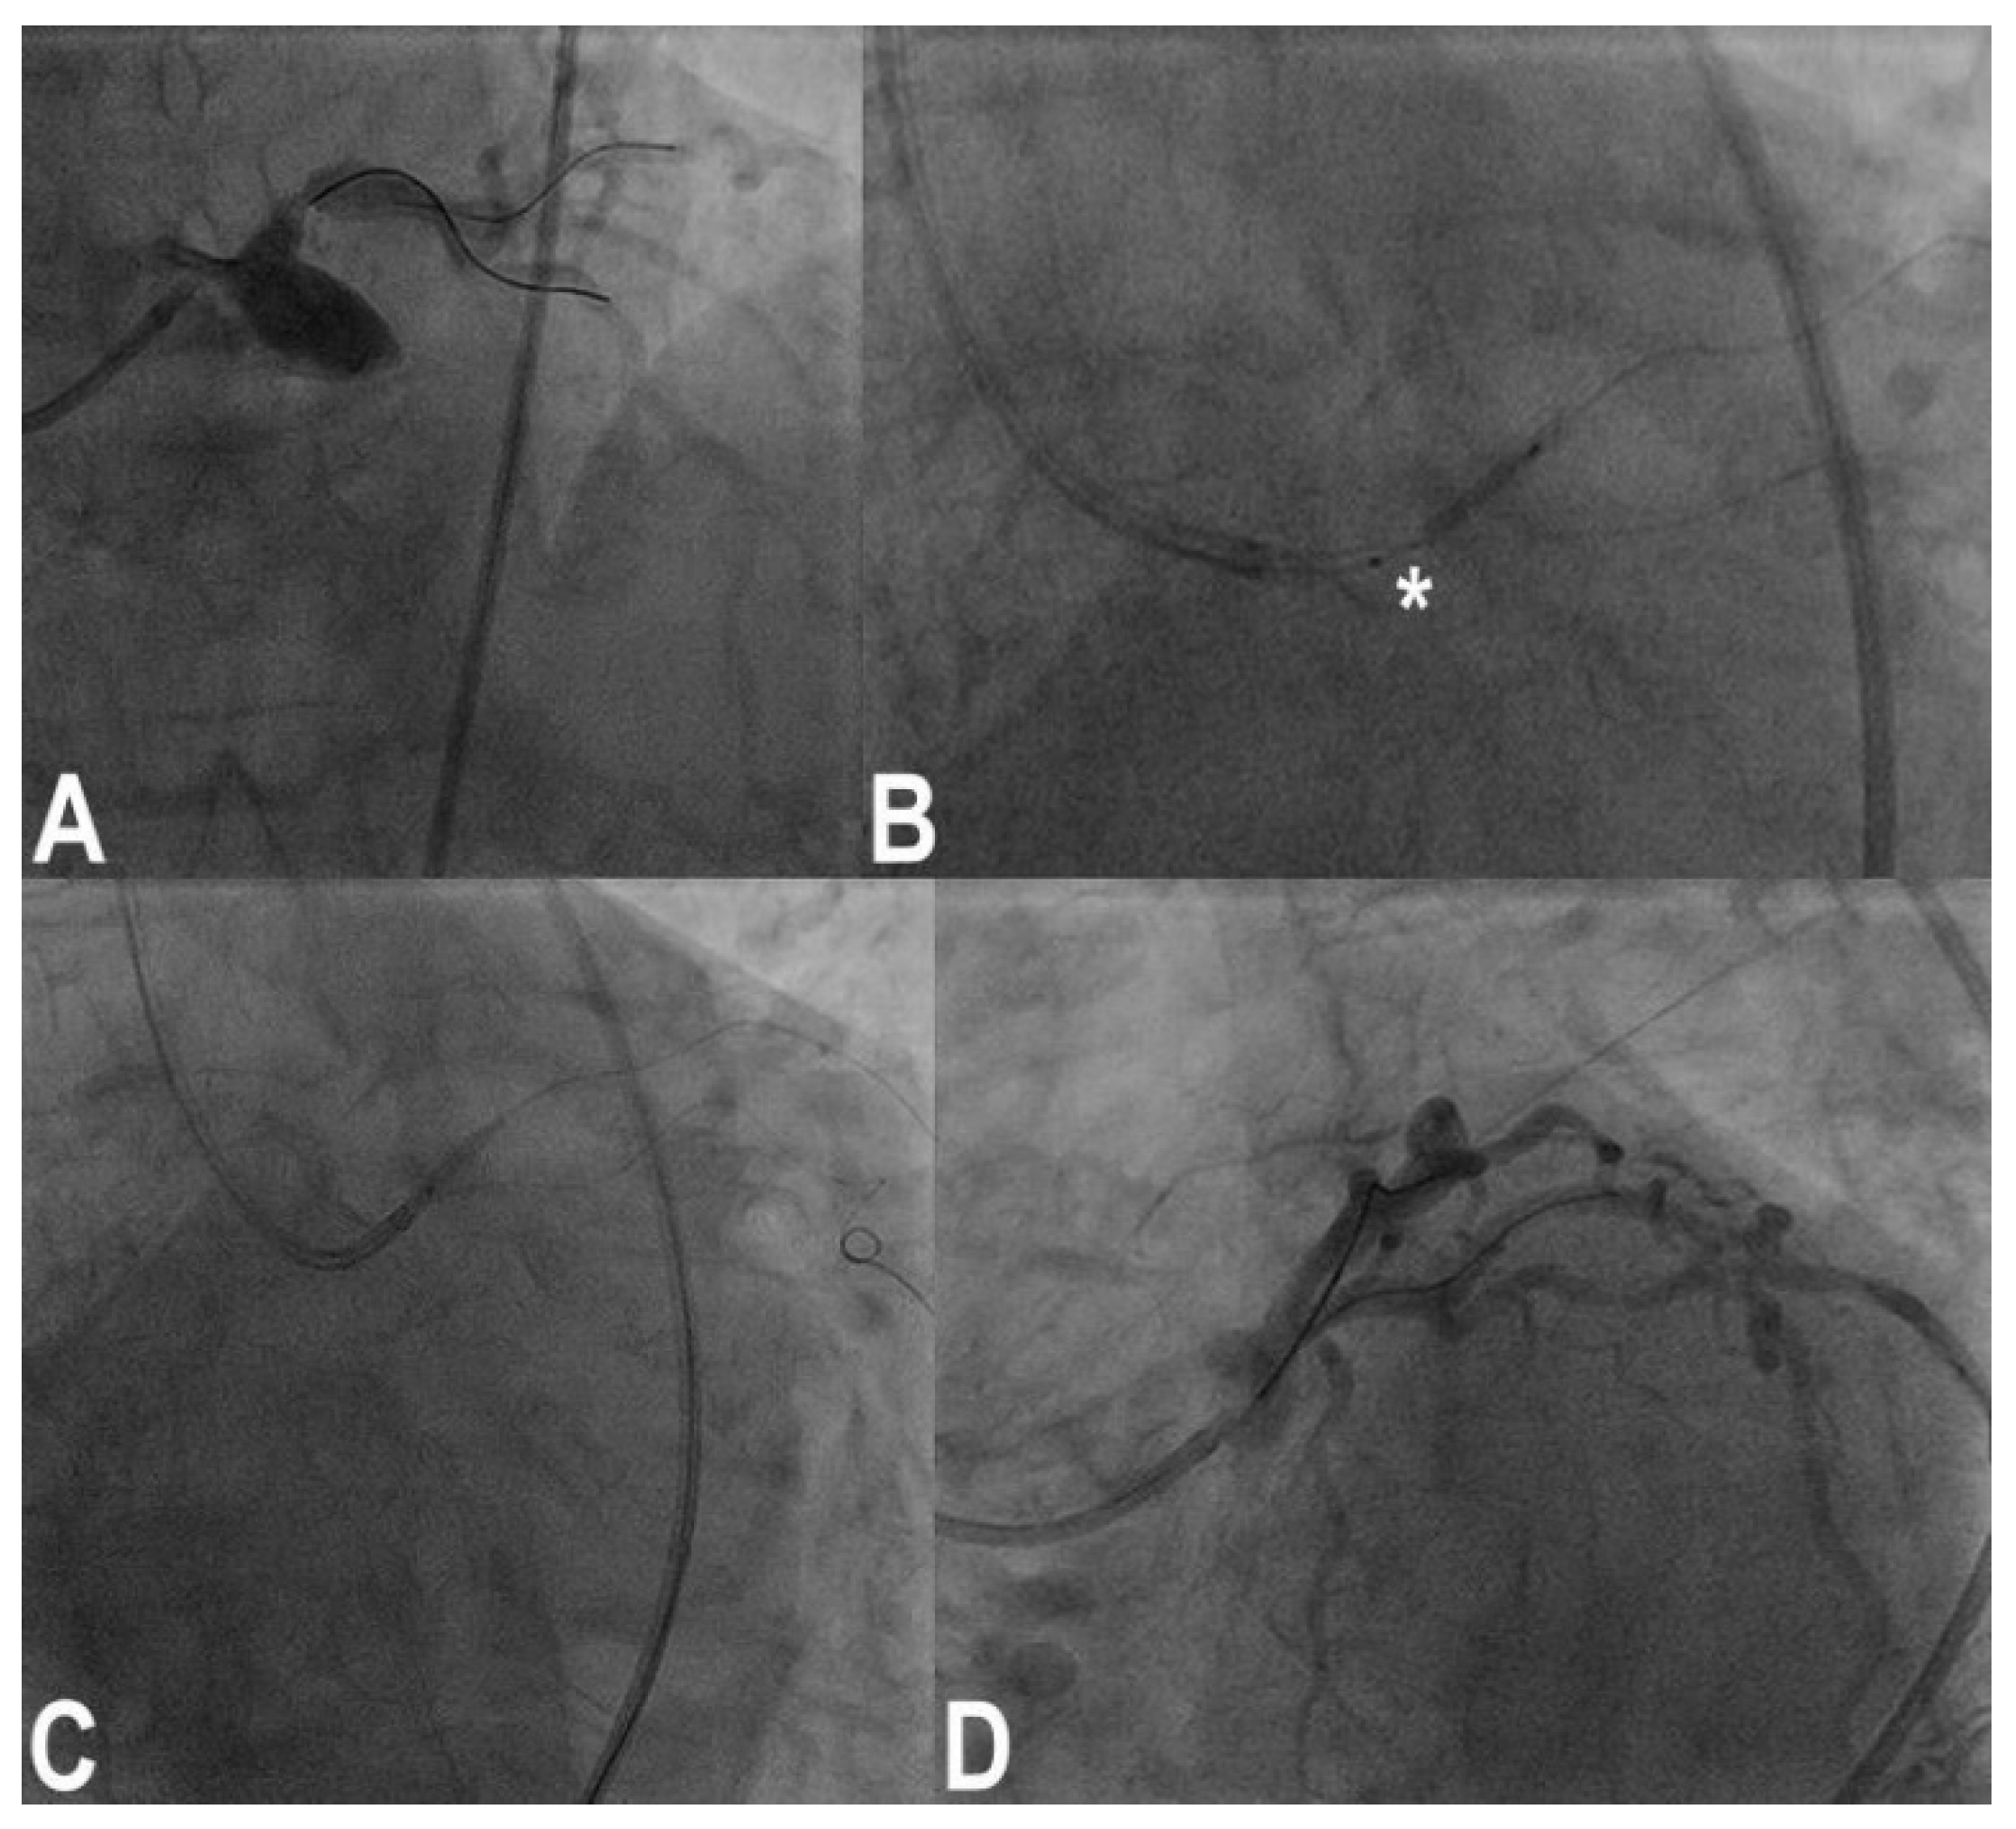

3.11. Stent Loss

3.12. Stent Underexpansion